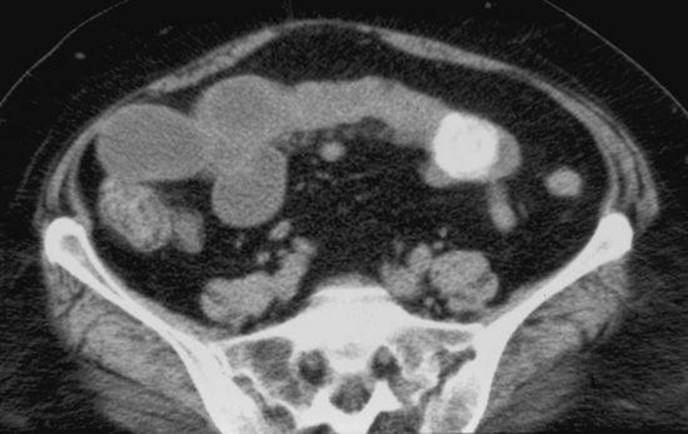

A 37-year-old woman presents with a history of intermittent severe upper abdominal pain and a more recent problem of persistent abdominal distension with associated nausea and vomiting. What complication of gallstone disease is being demonstrated in the CT image below?

Figure 39-1

Gallstone ileus from a large gallstone obstructing the mid-ileum.

What is the most common location of a bowel obstruction in patients with gallstone ileus?

Characteristically, the obstruction occurs in the terminal ileum where the lumen is the narrowest. The majority of patients with gallstone ileus are women and older than 70 years. Recurrent gallstone ileus may occur in approximately 5% of patients and a search should be made for an additional stone(s) during surgery.